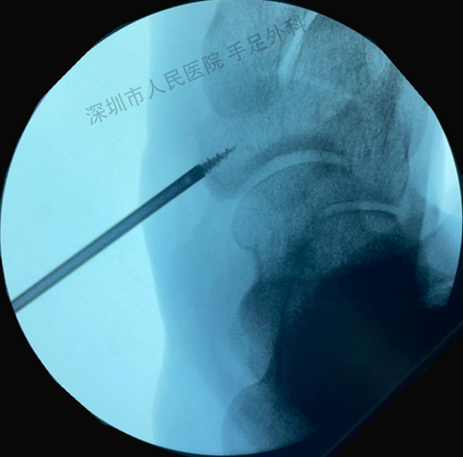

图7:切除副舟骨